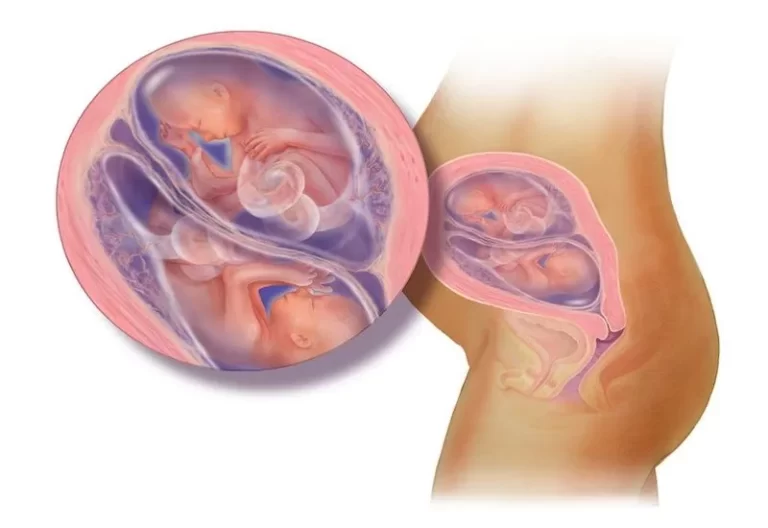

Đa ối là gì?

Đa ối là tình trạng:

👉 Lượng nước ối nhiều hơn mức bình thường trong thai kỳ

Bác sĩ thường đánh giá qua chỉ số:

- AFI (chỉ số nước ối)

📌 Thông thường:

- AFI: 5–25 cm → bình thường

- AFI > 25 cm → đa ối

3. Mang đa thai

- Song thai dễ gặp đa ối hơn

Đa ối ảnh hưởng đến thai nhi như thế nào?

Trong đa ối nhẹ:

👉 Hầu như không ảnh hưởng

Trong đa ối nặng:

- Nguy cơ sinh non

- Thai không đúng ngôi

- Biến chứng khi chuyển dạ

👉 Quan trọng nhất là:

Theo dõi sát và xử lý kịp thời